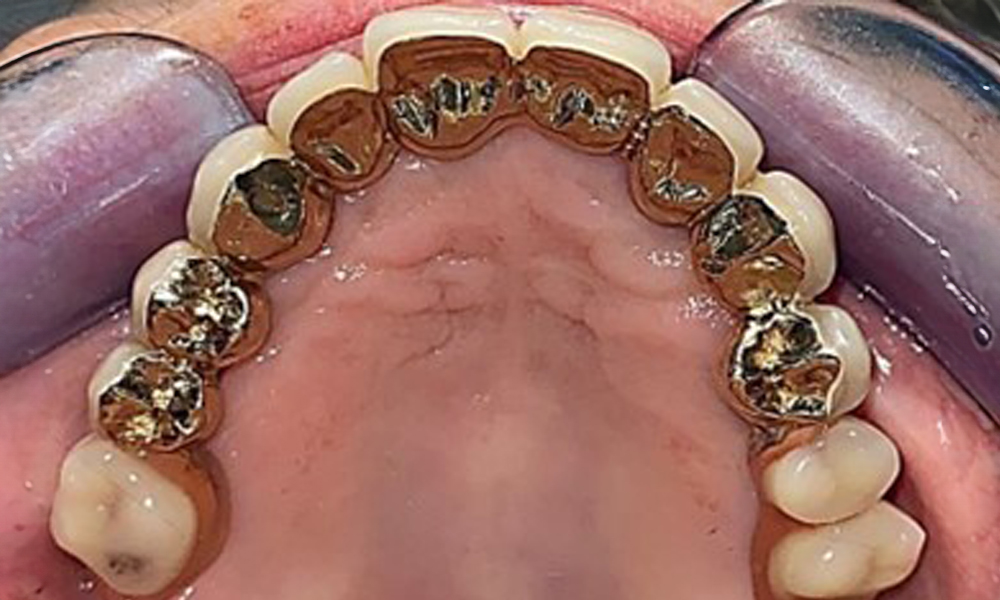

Okklusalansicht: Oberkiefer mit herausnehmbarer, gaumenfreier Prothese.

Abb. 3 Okklusalansicht: Oberkiefer mit herausnehmbarer, gaumenfreier Prothese.

Die Mundschleimhaut ist auf mögliche Pilzinfektionen und Druckstellen zu untersuchen. Der Zahnersatz muss optisch auf Sauberkeit geprüft werden. Im vorliegenden Fall zeigen sich interdental Verfärbungen, welche auf den Teekonsum zurückzuführen sind (Abb. 7). Der Zahnersatz sollte in der Praxis professionell gereinigt werden in entsprechenden Desinfektions- und Reinigungsbädern.

Zahnersatz von Basal zur Beurteilung auf Sauberkeit.

Abb. 7: Zahnersatz von Basal zur Beurteilung auf Sauberkeit.